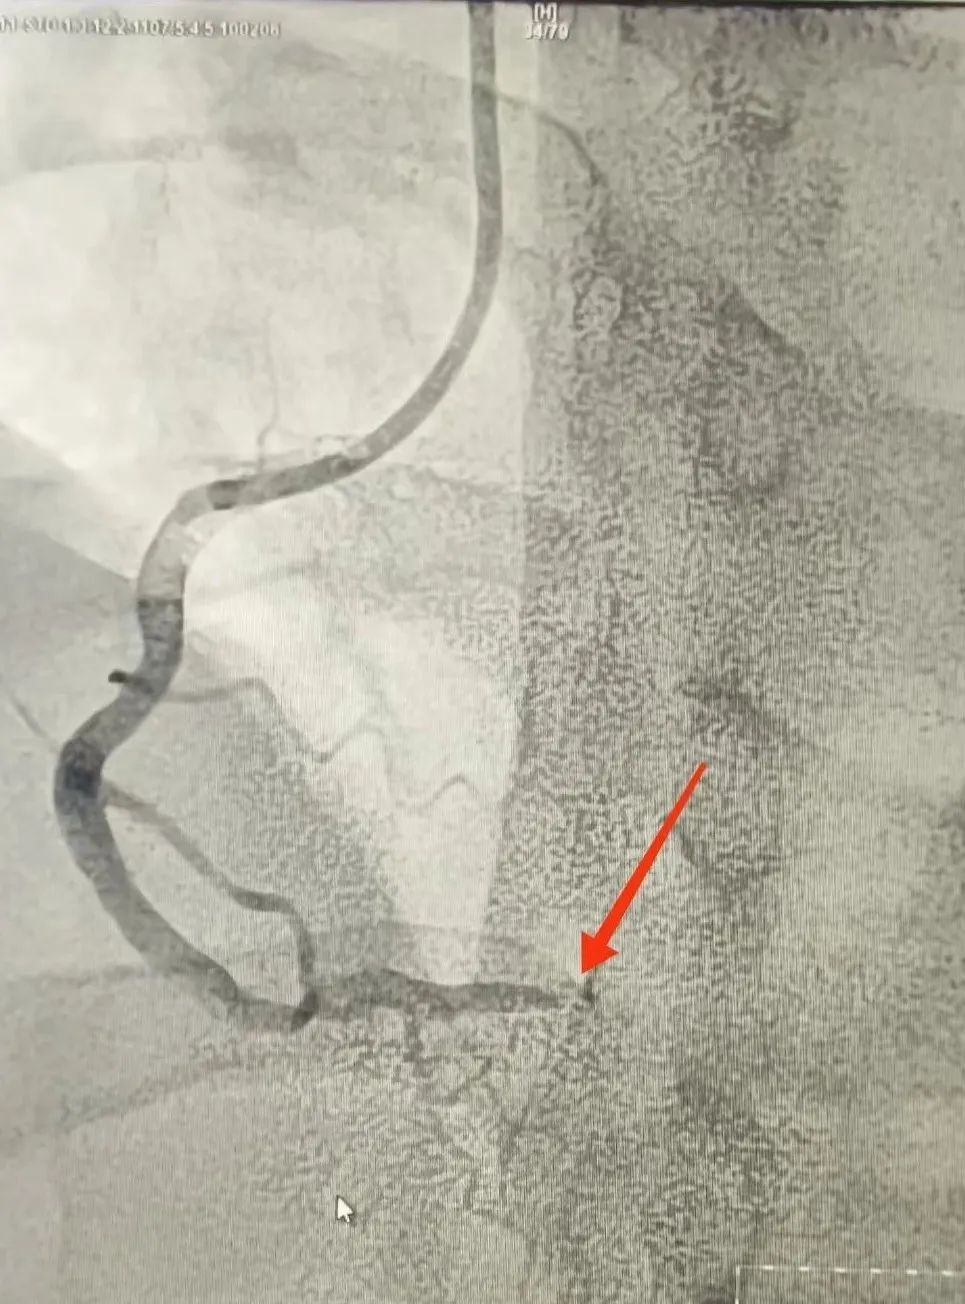

120救護車(che)到(dao)達蘇州九龍醫(yī)院後(hou),龍先(xian)生(sheng)直接被送到(dao)急診搶救室。醫(yī)護人(ren)員(yuan)立即對其完善(shan)相關檢(jian)查。心電(dian)圖提示:窦性心律,1度房室傳(chuan)導(dao)阻滞,II、III、AVF導(dao)聯(lian)ST段擡高(gao);考慮“急性心肌梗死”。情況十分(fēn)緊急,心血筦(guan)內(nei)科(ke)劉廣(guang)安(an)副主(zhu)任醫(yī)師團(tuán)隊(duì)來到(dao)急診搶救室會診,立即啓動(dòng)胸痛中(zhong)心綠色生(sheng)命通(tong)道,直達導(dao)筦(guan)室進(jin)行心髒血運重(zhong)建(jian)!急診“冠狀動(dòng)脈造(zao)影CAG術(shù)”提示:RCA遠(yuǎn)段完全閉塞,血流TIMI 0級;LAD狹窄30%,LCX遠(yuǎn)段狹窄40%。鑒于(yu)患者年(nian)紀輕且病情急,專(zhuan)傢(jia)團(tuán)隊(duì)決定爲(wei)其采用(yong)藥物(wù)球囊PTCA治療。藥物(wù)球囊手術(shù)通(tong)過(guo)向病變血筦(guan)部(bu)位輸(shu)送藥物(wù),達到(dao)擴張血筦(guan)、抑製(zhi)血筦(guan)再狹窄的(de)效果。這種手術(shù)方(fang)式(shi)創傷小(xiǎo)、恢複快,适郃(he)年(nian)輕患者咊(he)需要避免長(zhang)期支架植入的(de)患者。

術(shù)前(qian)

術(shù)後(hou)